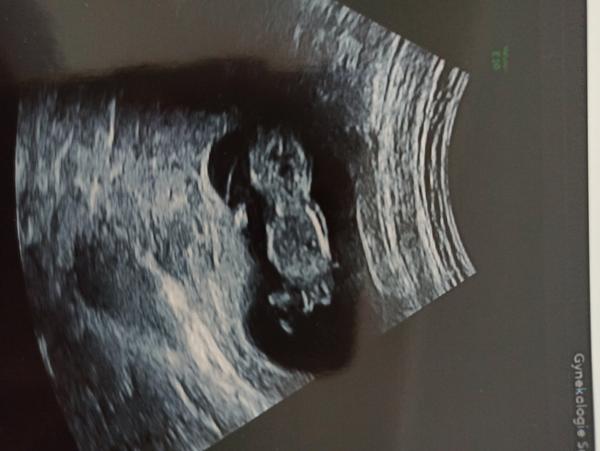

11+5 utz - je to holka. Mám s tím počítat?